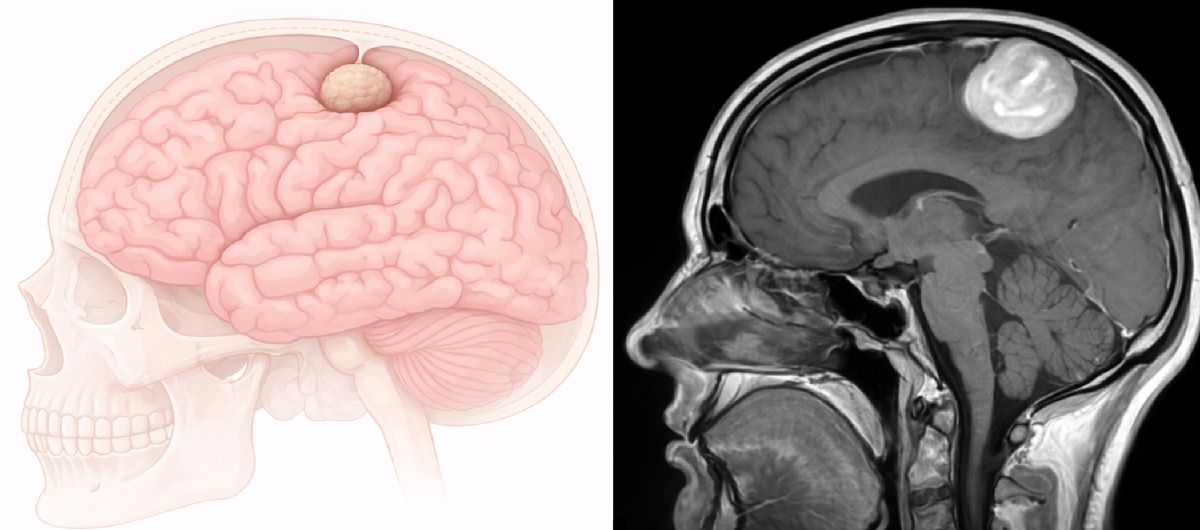

To má zásadní důsledek pro jeho chování. Protože nádor vyrůstá „zvenčí“ a na mozek tak tlačí, místo aby do něj prorůstal, bývá často dobře ohraničený (patrné na fotografii po vyjmutí nádoru na mém Instagramu). Na zobrazovacích metodách působí jako kulovitý či oválný útvar přisedající k lebce. Většinou neproniká do mozkové tkáně, ale utlačuje ji, podobně jako když pomalu rostoucí kořen stromu nadzvedává chodník, aniž by jej poškodil zevnitř.

Vlevo ilustrativní zobrazení meningeomu utlačujícího mozkovou tkáň. Vpravo snímek z magnetické rezonance.